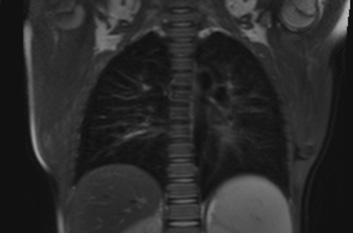

Рис 3. Т2-взвешенное изображение легких ребенка.

Цель: Разработка и внедрение в клиническую практику МРТ-исследований легких. Описание проекта: В настоящее время пациенты с сочетанной травмой обследуются методами многофазной компьютерной томографии с введением контрастного препарата. При этом пациент получает значительную дозу облучения: по медицинским показаниям, исследования могут регулярно повторяться. В то же время, МРТ позволяет без лучевой нагрузки получить изображения с различными типами контраста, что позволяет дифференцировать характер патологии. Традиционно считается, что МРТ не обладает достаточной чувствительностью при обследовании легких, однако современные методики МРТ позволяют получать диагностически информативные изображения – как при задержках дыхания(чтобы избежать артефактов движения), так и при свободном дыхании пациента. Задачей исследования является разработка и клиническая апробация МРТ протоколов сканирования легких. Результаты: Разработаны протоколы сканирования, ведется клиническая апробация.